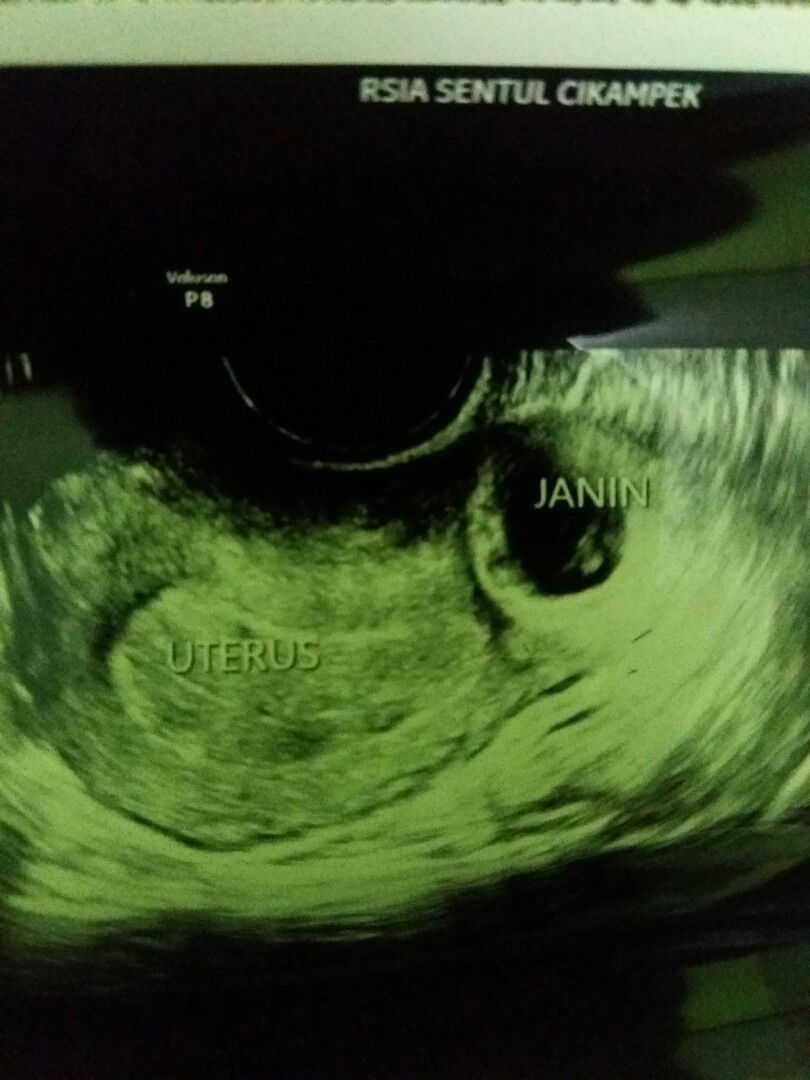

Teringkat...kalau ada sekarang sudah 9bulan dan mungkin sedang kontraksi"nya 😣. Ini foto bakal janin Bun..tapi sayaang bukan pada tempat nya (rahim) tapi di tuba falopi.. Hamil ektopik/hamil di luar kandungan.. Sharing yu bun'siapa tau disini ada yg pernah mengalaminya?

Assalamuallaikum. Akhir nya selama perjalanan 8wk,dd ga kuat di dalam perut ibu,allah lebih sayang dd. Pasca di fonis hamil di luar kandungan usg pertama ,dd masih hidup 8wk. Kata dr spog. Dd nya kuat masih hidup dj nya baik dan perkembang ,tapi ini terpksa akan di kiret ,karna membahakan ibu nya nanti bisa pendarahan hebat. Biasa nya kasus ini dd nya g akan hidup,berhubung masih hidup di suruh cek up 1 minggu. Blm 1 minggu -3 harilah perut terasa sakit pendarahan ,banyak sekali darah. Tak lama gumpalan keluar sebesar 2 jari, Langsung panik dan akhir nya lngsung pergi k rs,dan langsung masuk IGD,dan di situ keluar lagi kumpalan sama seperti yg pertama,. Menurut dr itu jaringan nya sudah keluar. Dan perut akupun di pencet2 di tekan2 oleh dkter ternyata tidak sakit,suster bilang "ko ga ada yg sakit y bu. Langsung lah saya di pasang, infus tensi saya tinggi. Selah itu usg kembali, ternyata dd nya masih hidup,dj nya baik,berkembang'dr pun merasa aneh kmbali ko ini hidup,padahal jaringan nya sudh keluar.. Usut punya usut usg tranvagina deh,ia hasil nya sama. Akhir nya dr memutuskan aku di ruang inapkan dulu 1 hari ,karna masih pendarahan tapi tidak di sertai nyeri. Ke esokn hari nya di ck up lagi dan hasil nya sama pd usg yg k 2. Akhir nya dokter perlu pertimbangan,memutuskan ini di operasi tidak bisa di kiret,karna dd nya masih hidup. Selang bbrapa jam kluarga ambillah k putusan yg disarankan dr untuk di op. Rasa nya pertama kali dlm hidup masuk ruang op,hidup terasa akan berhenti cukup sampe disini. . Sudah di bius setngah mulai lah op di mulai dan aku melihat dokter menyayat2 perut,di tarik2,dan dr pun bilang bu dd nya kuat sekali ya,ini sudah tipis sekali bentar lagi akan pecah. Di situ aku di ajak ngobrol sama dr khusus biusan. Bu tidur aja gpp sambil di memasukan cairan k infus. Ahhir nya akupun tertidur,ntah apa yg dy masukan mungkin bius tidur. Sadar aku sudah di ruangab tensi. Begitulah cerita pengalaman ku bun. Ibu sayang dd ?

Assalamuallaikum. Bunda bagi pengalaman. di jam subuh bangun sekitar jam 5 untuk k toilet. Di cek flek tidak terlalu banyak,. Jam 7 k toilet lagi di cek ternyata makin banyak ?. Akhir nya jam 8 saya memutuskan cek k dr kandungan. Pas di cek usg bisa alhamdulillah bayi nya berkembang baik,detak jantungpun sudah terdeteksi karna sudah masuk 8wk,dan baik. Tapi.. Dokter bilang ada yg jangagal kandungan saya. Akhir nya dtrasvagina. Dan hasil nya benar saja ,kata dr "ini hamil di luar rahim"tapi aneh nya janin sehat ini kejadian langka. Bisa nya ga akan hidup . Dokter menyarankan cek up 1 minggu kemudian Dokter memfonis jika saya pendarahan hebat dan nyeri terpaksa di kuret,janin di angkat. Dan dok terjuga memfonis. Ini pasti janin akan kami angkat.. *hati saya hancur stlah mendengar dokter bilang seperti itu,.. Apa kah disini bunda2 ada yang pernah mengalami seperti saya hamil di luar rahim? Apakah bisa akan masuk k rahim nnti nya? Saya berharap,Besar. Itu hanya fonis dokter,jika allah menghendaki saya hamil.allah maha membolak balikan semuah telak tangan ??